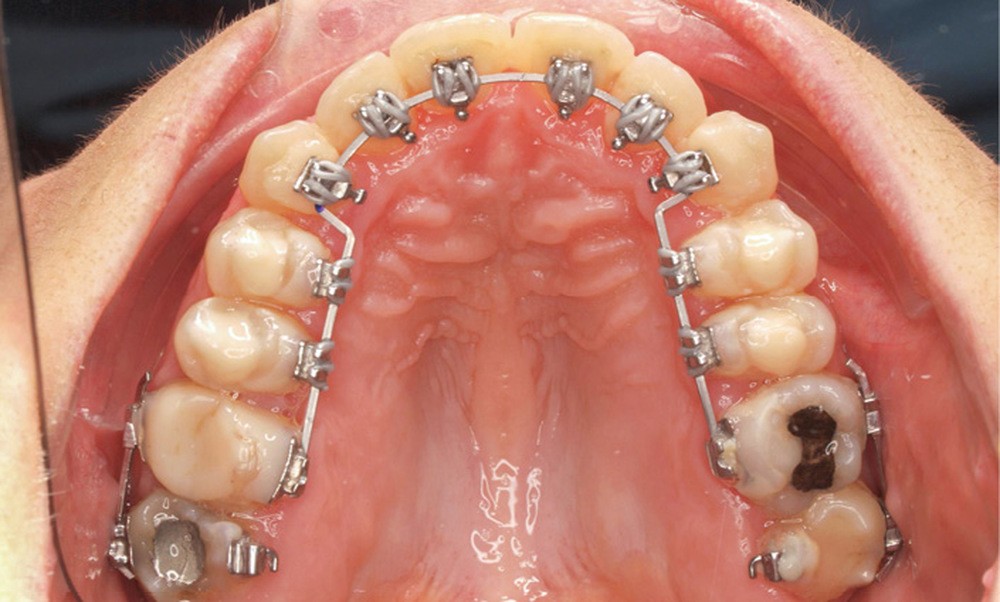

Correction

Le traitement est effectué avec un appareil lingual bimaxillaire et des attaches en .018 x .025 à insertion horizontale. L’appareil est réalisé intégralement au cabinet à partir d’un set-up conçu selon les objectifs décrits.

- Premier rendez-vous (fig. 2a) : l’arcade maxillaire est appareillée et un arc NiTi .014 en expansion est placé. L’arcade mandibulaire reçoit des cales rétro-incisives pour lever l’occlusion inversée. Par confort, des cales prémolaires, sans contact avec les dents antagonistes, sont posées pour réduire l’inocclusion latérale.

- Deuxième rendez-vous (fig. 2b) : les dents restantes sont collées et le même arc NiTi .014 est maintenu. Les cales rétro-incisives sont déposées et l’arcade mandibulaire est collée, un arc NiTi 0.014 posé.